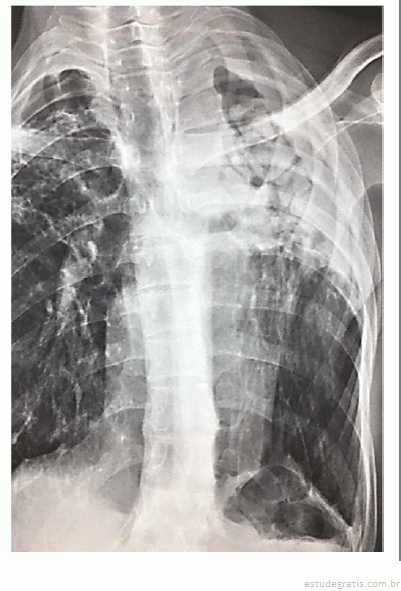

Paciente do sexo masculino, de 54 anos de idade, motorista de ônibus, foi encaminhado a consulta de ambulatório em serviço terciário para avaliação de hemoptise. Relatou dois episódios de moderada quantidade, aproximadamente 1 colher de sopa, de sangue vivo. O primeiro episódio ocorreu havia 3 meses e, o último, havia 2 semanas. O paciente nunca apresentou dispneia associada ou necessitou de atendimento em emergência. Era tabagista em remissão havia 5 anos, quando foi diagnosticado com tuberculose pulmonar, tratada com tuberculostáticos por 6 meses, sendo considerado curado. A imagem a seguir mostra o Raio X de tórax do paciente.